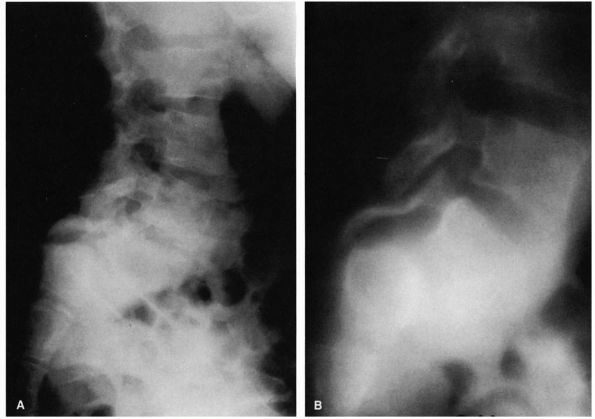

FIGURE 16-24. (A)

Nineyear-old girl with type I spondylolisthesis. Note how pars interarticularis has become attenuated, allowing for severe slippage (translation and angulation). The entire posterior arch has slipped forward. (B) Polytome demonstrating the elongation of pars interarticularis. |